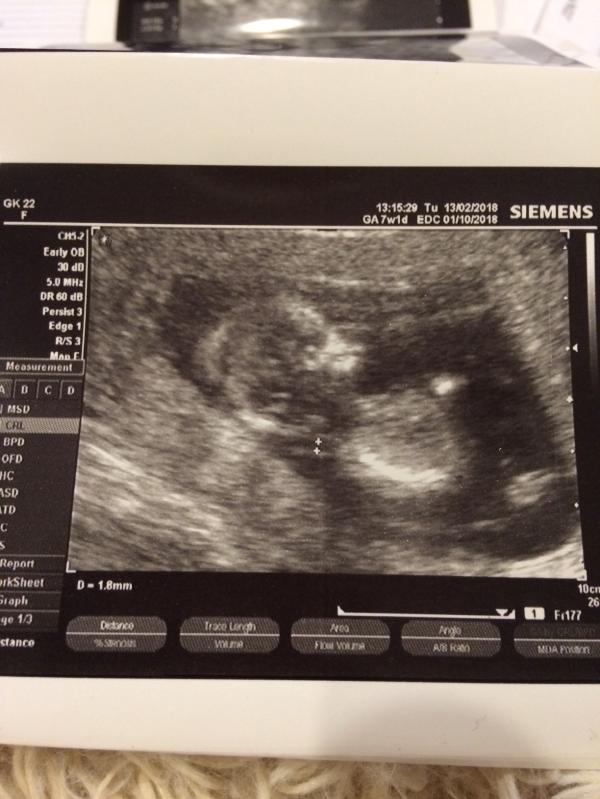

Ну вот и прошёл первый самый сложный триместр !!!в ожидании чуда !!!

@marian2, да это УЗИ с 1 скрининга ,а так уже щас 20 неделя идёт

Это УЗИ с первого скрининга? А так уже половина прошла!!!

12 недель это же первый